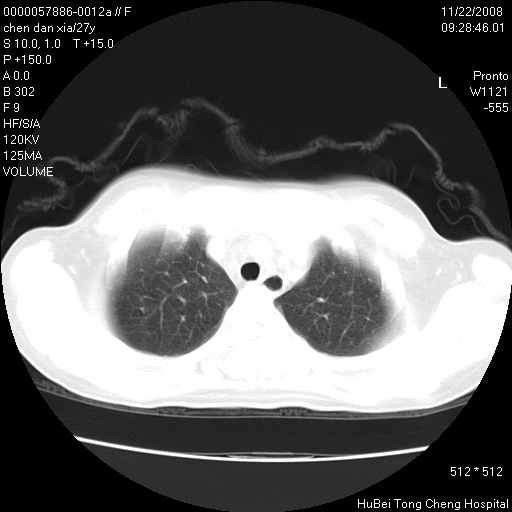

标题: CT16752:F,27Y。发热咳嗽20余天,伴盗汗。 [打印本页]

标题: CT16752:F,27Y。发热咳嗽20余天,伴盗汗。

考虑双肺粟粒性肺tb,右侧胸膜增厚.

气管前腔静脉后淋巴结肿大 右肺门纹理模糊

淋巴结核?

右下肺见片絮状影,两肺野内分布不均的小结节影,结核并肺内播散可能性大,建议结合实验室检查 .

右下肺纹理模糊;纵隔可见肿大淋巴节;右心缘旁结节,边缘光滑,纵隔窗病变范围较肺窗明显小,首先考虑右下肺结核,不排外淋巴瘤

双肺纹影普多,部分呈网状,支炎或淋巴管炎?

纵隔内淋结肿

局部胸膜增厚

下肺结节,结节内钙化,肺门纵隔淋巴肿大 结核可能性大

似有粟米状结节。考虑粟粒型肺结核?

1)考虑两肺感染性病变。2)纵隔淋巴结肿大。